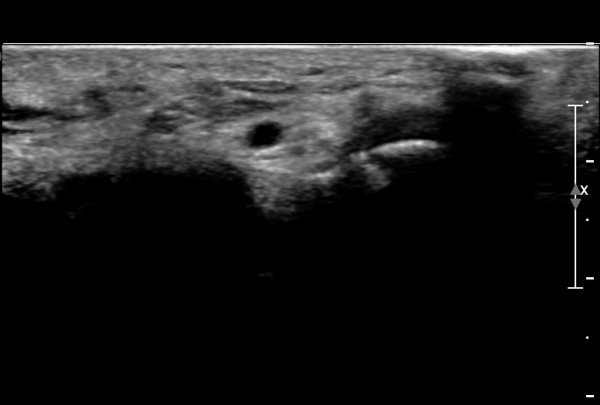

ŽÃËÀÚ¸¦ ¾à°£ ¸»´ÜÀ¸·Î À̵¿ÇÏ´Ï ¿¬ºÎÁ¶Á÷ ºÎÁ¾ÀÌ ´õ¿í ½ÉÇÏ°Ô °üÂûµÇ°í(»çÁø 2),